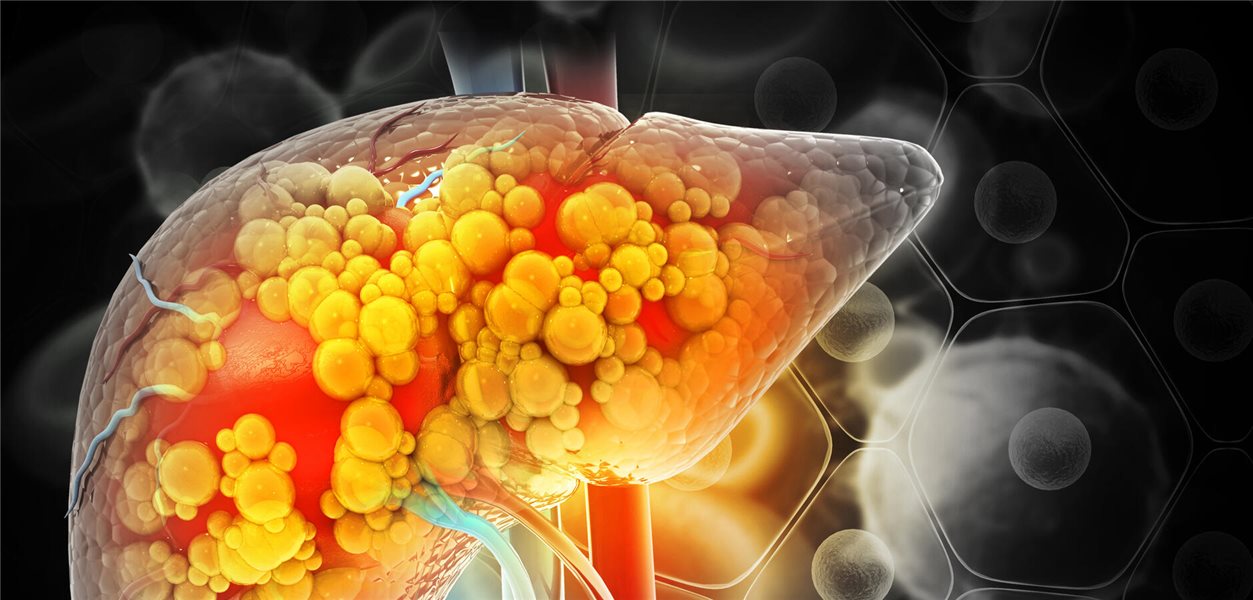

Did you know that up to 70% of individuals with rheumatoid arthritis experience some form of non-alcoholic fatty liver disease (NAFLD)? The rising prevalence of metabolic syndrome, coupled with the side effects of medications like methotrexate, is creating a complex health landscape for those managing rheumatic conditions. This article delves into the intertwined relationship between methotrexate, liver health, and future treatment strategies.

For years, when liver values spiked in patients undergoing methotrexate treatment, hepatotoxicity was immediately suspected. However, emerging research reveals a more nuanced picture. Often, the underlying cause isn’t solely the medication itself, but rather pre-existing conditions like fatty liver disease and metabolic syndrome, which can increase the risk of complications. This understanding is crucial for more accurate diagnoses and better patient care.

Many patients with rheumatoid arthritis, psoriatic arthritis, or lupus have an increased risk of metabolic syndrome, a cluster of conditions including high blood pressure, high blood sugar, unhealthy cholesterol levels, and excess abdominal fat. These metabolic factors can contribute to the development of NAFLD, making the liver more vulnerable to the potential effects of medications.